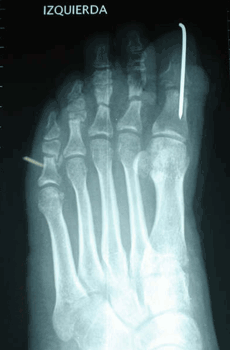

Caso 2: Hallux Valgus del Adolescente

Pie Izquierdo operado